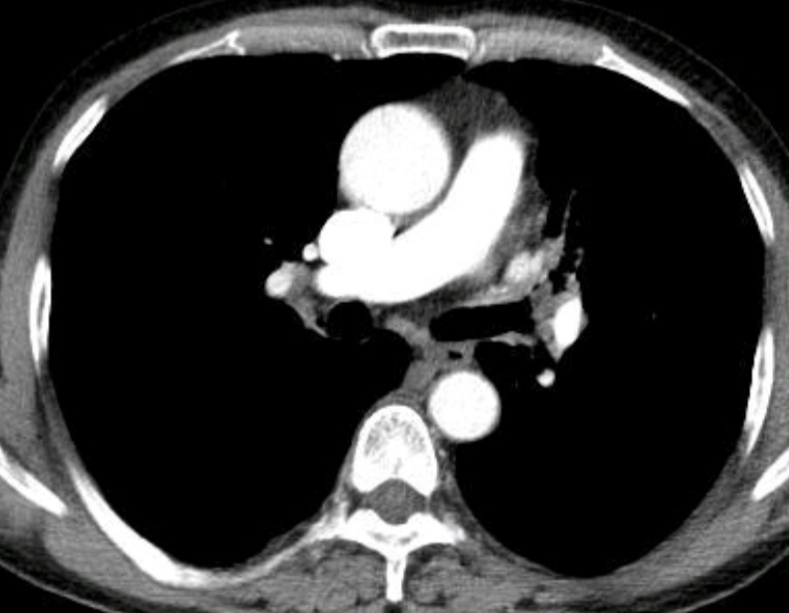

经专家再次会诊,决定进行第二次支气管镜检查并清除气道内新生物,为了保证手术安全性和效果,检查时采用了全麻硬质气管镜和可弯曲支气管镜结合的手术方式,成功冷冻取出支气管病变,发现竟是被坏死物包裹的半块花生米。